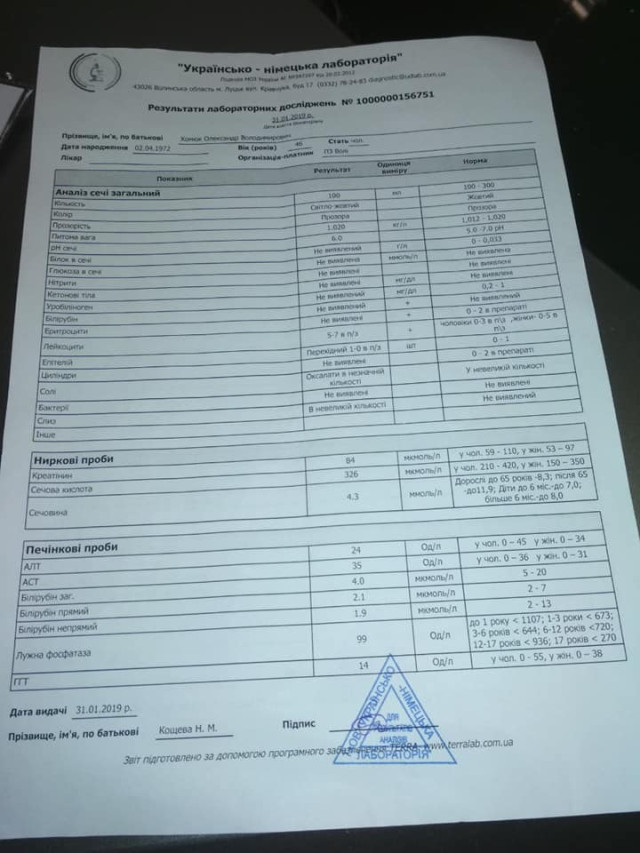

Волинянин Олександр Хомюк потребує допомоги у боротьбі з раком.

Як повідомили його близькі у Фейсбуці, у нього негоджкінська лімфома великих клітин В, початок 4 стадії.

Як повідомили його близькі у Фейсбуці, у нього негоджкінська лімфома великих клітин В, початок 4 стадії.